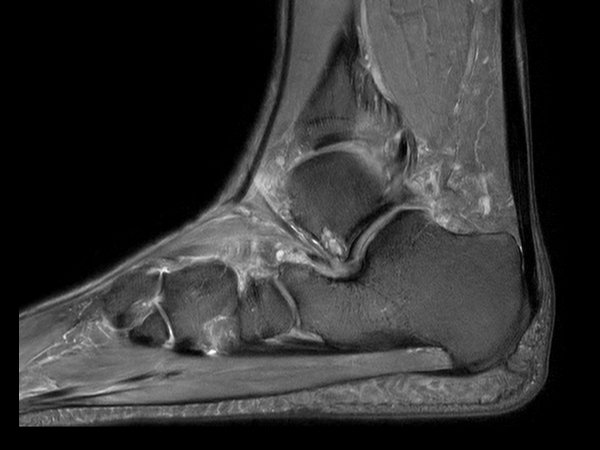

Sagittal PDw TSE mDIXON XD (In Phase)

Sagittal PDw TSE mDIXON XD (Partial FatSat)

Sagittal PDw TSE mDIXON XD (Water only)